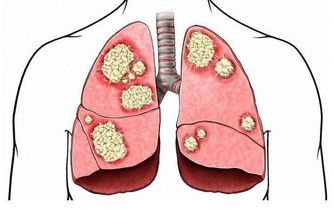

如果身體某一部位突然疼痛,持續一個多星期,應盡快查明原因。例如,長期腹痛是大腸癌的症狀;胸痛可能是肺癌引起的;骨痛可能是癌症轉移的症狀。這時,我們應該去醫院找醫生檢查一下。